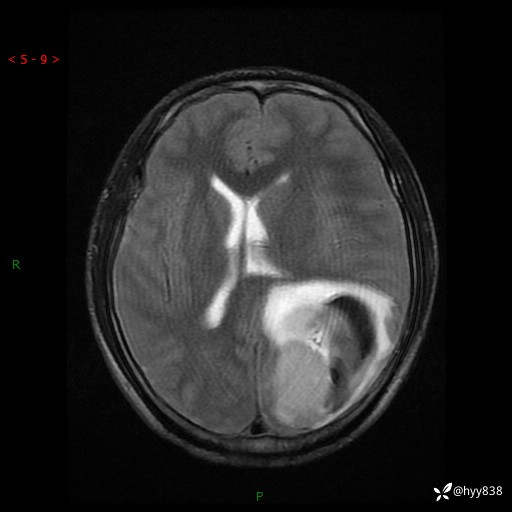

病例年轻小伙,头痛伴呕吐半年,渐进性加重1月。疑难病例,第一次见--结果公布~

性别:男

年龄:21岁

简要病史:头痛伴呕吐半年,渐进性加重1月

颅脑MRI平扫+增强